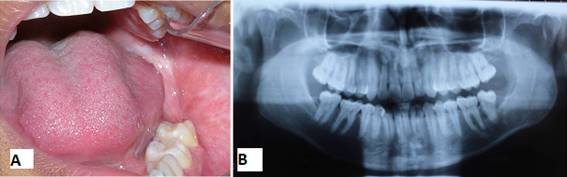

The patient was followed up clinically and radiographically every three months for one year and then annually for five years. Figs 20 A and 10 B show the final clinical and radiographic appearance five years after surgery, where complete bone neoformation is observed.

After this follow-up period, the patient was discharged as there was no clinical-radiographic evidence of recurrence.